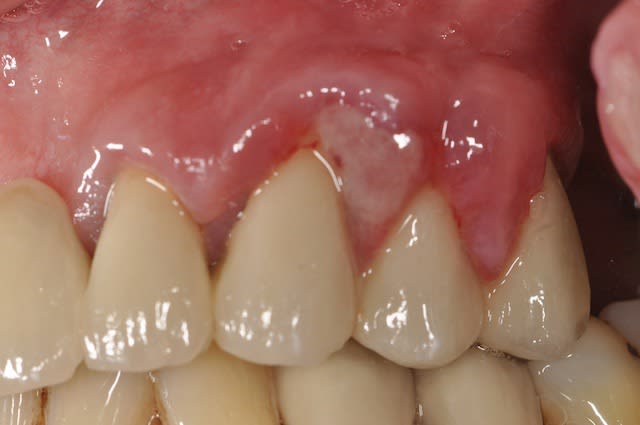

Je viens de recevoir un patient sur qui a été posé un bridge maxillaire de 11 éléments il y a un an.

3 mois après la pose il me dit qu'il y a eu une spectaculaire réaction gingivale sur le secteur 1. Le praticien qui a posé n'a pas pu posé de diagnostic. Le patient n'avait aucune douleur mais des saignements abondants dans ce secteur. Puis le problème a disparu comme il était venu.

Aujourd'hui, même chose mais du coté gauche. Aucune douleur mais un inconfort et les mêmes saignements.

J'ai recherché une fêlure en sondant... mais la gencive était hypertrophiée et les valeurs n'ont pas de sens. Ce sont des pseudo-poches.

Ce que je trouve étrange c'est que la gencive ne fasse pas mal et cet aspect blanc fibrineux

Ca ressemble à un bête abcès paro, sauf qu'on a effectivement du mal à en trouver la cause... L'ajustement du bridge n'est pas parfait, de là à ce qu'il soit responsable... Tassements alim sous le bridge? Suffirait d'un débris alimentaire qui reste coincé un jour sous un inter pour créer ce genre de chose.

Ben les 2 mon capitaine l'ajustement n'est pas top au niveau 23,24,25 et l’hygiène n'est pas top non plus : praticien 1-patient 1 : Balle au centre.

Ce "beau" bridge est voué à l'échec...

L'adaptation est mauvaise (et je reste gentil)

La paro va s'installer, il est clair que l'entretient est perfectible, mais le bridge en est la cause.

le patient a de multiple récessions, l'état paro est pas top en général.

Je pense moi aussi que le bridge est en cause : il est mal adapté du coté droit comme du coté gauche. Mais alors pourquoi la réaction gingivale n'est pas survenue des deux cotés en même temps?

Pour répondre à G-P, pour moi, le critère de parodontite est la perte osseuse. Là, je pense qu'on a un problème de gencive, pas osseux.

Pourtant sur tes radios on voit très clairement une perte osseuse verticale, résiduelle ou évolutive, là est la question.

On voit aussi nettement des gros problèmes d'adaptation du bridge, susceptibles de favoriser la rétention de plaque de et débris alimentaires.

Paro pire secteur 1 au début car bridge super mauvais de ce côté, mais plus de place pour nettoyer. Secteur 2, moche, mais moins pire, mais pas de place pour nettoyer.

empiètement dans l'espace biologique nécessaire . C'est à dire finition trop sous-gingivale